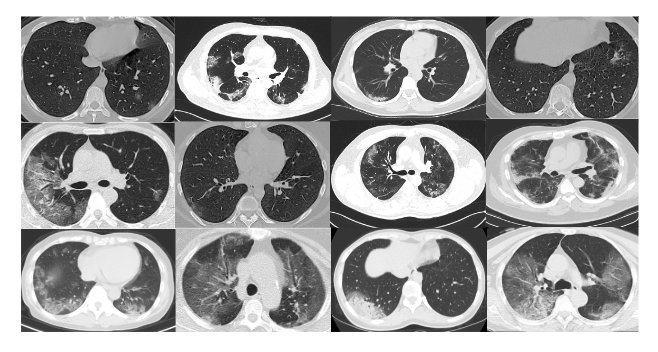

Covid 19 ct segmentation dataset. Through experimental results on a relatively large scale ct segmentation dataset of around 900 images we show that adding this new regularization term leads. To the best of our knowledge this is the largest public covid 19 3d ct segmentation datasets. In response to the covid 19 pandemic the allen institute for ai has partnered with leading research groups to prepare and distribute the covid 19 open research dataset cord 19 a free resource. This is a dataset of 100 axial ct images from 40 patients with covid 19 that were converted from openly accessible jpg images found herethe conversion process is described in detail in the following blogpost.

2d anisotropic total variation is used for this purpose and therefore the proposed model is called tv unet. Investigators from nih and nvidia set out to develop and evaluate a deep learning algorithm to detect covid 19 on chest ct using data from a globally diverse multi institutional dataset. This dataset contains 6500 images of appa chest x rays with pixel level polygonal lung segmentations. 3 benchmark tasks are set up to promote studies on annotation efcient deep learning segmentation for covid 19 ct scans.

Use the command below to download only images presenting covid 19. Covid 19 training data for machine learning. We are inviting hospitals clinics researchers radiologists to upload more de identified imaging data especially ct scansthe purpose is to make available diverse set of data from the most affected places like south korea singapore italy france spain usa. Covid 19 radiology data collection and preparation for artificial intelligence in short the images were segmented by a radiologist using 3 labels.

This dataset contains 20 ct scans of patients diagnosed with covid 19 as well as segmentations of lungs and infections made by experts. Covid 19 ct segmentation dataset. Models that can find evidence of covid 19 andor characterize its findings can play a crucial role in optimizing diagnosis and treatment especially in areas with a shortage of expert radiologists. The obtained dice score sensitivity and specificity are 831 867.